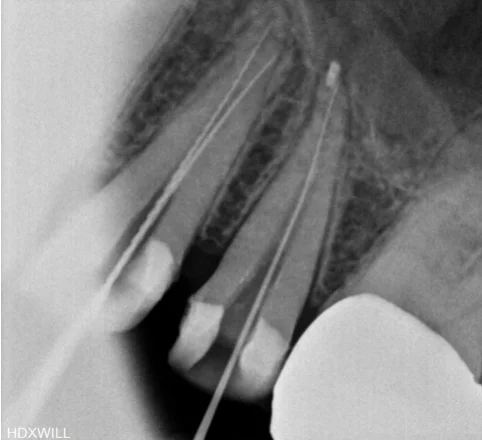

오산 재신경치료 이미 치료한 치아의 통증, 기둥이 세워진 경우 안녕하세요. 서울버팀치과 엄용국 원장입니다. 오늘은 한 환자분의 사례를 소개해 보려고 합니다. 신경치료를 받았던 치아에 다시 증상이 나타나 내원하신 경우였는데요. 신경치료가 끝난...

오산 재신경치료, 다른 치과에서 받았는데 계속 아프다면 안녕하세요. 오산 서울버팀치과 엄용국 원장입니다. “타 치과에서 신경치료를 받고 있습니다. 5~6번 정도 치료를 받았는데 아직도 가만히 있어도 아프고 불편합니다. 다른 치과에서 다시 진료를...